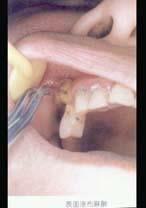

问题 7岁患儿下颌乳中切牙松动Ⅲ度、拔除时宜采用 ( )

选项 A.2%普鲁卡因浸润麻醉 B.2%丁卡因表面麻醉 C.2%利多卡因浸润麻醉 D.2%利多卡因阻滞麻醉 E.2%普鲁卡因阻滞麻醉

答案 B